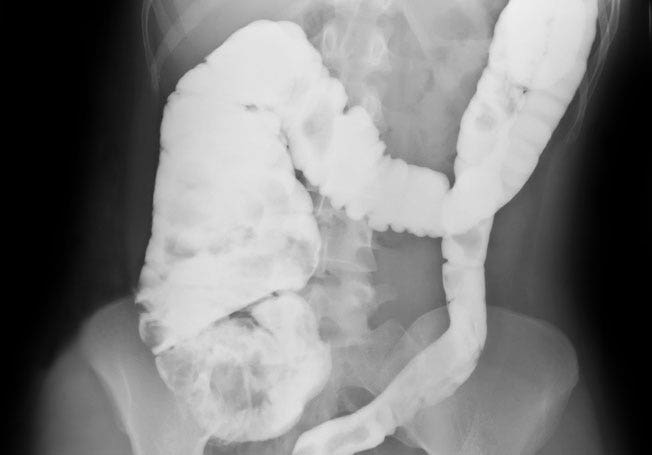

Developing a kinder, gentler alternative could have a huge impact on the number of people who got screened and potentially on those who were successfully treated. One such alternative has been dubbed the ‘virtual colonoscopy,’ which uses an X-ray CT scan and has shown to be effective at catching polyps, particularly larger ones. The CT scan avoids the use of the dreaded colonoscope, but until now, has also required the yucky bowel-cleansing drink.

A new study published in the Annals of Internal Medicine reports on 605 adults at moderate risk for colon cancer who used a laxative-free CT scan, followed a few weeks later by a regular colonoscopy. Subjects adhered to a low-fiber diet for two days, and the scan used computer-aided systems to virtually cleanse the images. The laxative-free CT scan was nearly as good as a regular colonoscopy at detecting larger lesions (the ones most likely to become cancerous) but not as good at detecting smaller suspicious lesions. It identified more than 90 percent of the common polyps that were 10 mm or larger.